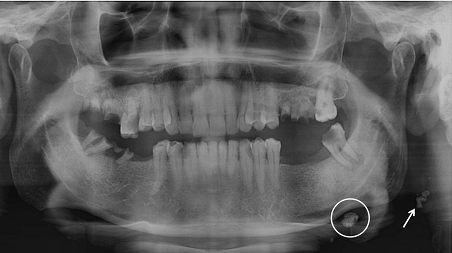

9. What condition can be seen in the following X ray? (the circle)